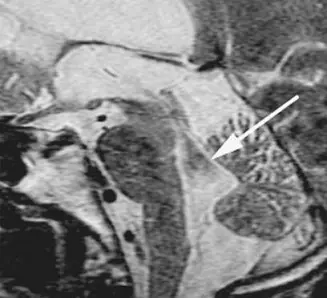

附圖中箭號所指示的暗灰色區域是下列何種現象產生的假影?

- 影像特徵與解剖構造:此圖為一張腦部正中矢狀面(mid-sagittal)的磁振造影 T2 加權影像(T2WI)。影像中可清晰辨識大腦皮質、中腦、橋腦、延腦等腦幹構造,以及後方的小腦。

- 異常信號表現:在 T2WI 中,靜止的腦脊髓液(如腦池內的液體)理應呈現高信號(亮白色)。然而,圖中白色箭頭所指的位置——即連接第三與第四腦室的大腦導水管(aqueduct of Sylvius)與第四腦室上半部——卻呈現一塊邊界不規則的暗灰色至黑色低信號區域。

- 物理意義:這種在 T2WI 上局部失去液體高信號的現象,是醫學影像中非常經典的「流動空洞」(flow void)徵象,主要起因於該處流體的快速且不規則流動。

- (C) turbulent flow artifact(紊流假影): 正確。大腦導水管是 CSF 通道中最狹窄處,液體在此處的流速最快,且受到心臟搏動週期的強烈影響,呈現強烈的脈動性。這種快速、多方向的流體運動會形成紊流(turbulent flow)。在 MRI 物理學中,同一體素(voxel)內的質子若具有多種不同的流速與方向,會導致嚴重的體素內相位失散(intravoxel dephasing),質子自旋相位相抵消而無法產生有效迴訊,最終在影像上形成暗黑色的無信號區。這即是流動空洞(flow void)產生的主因。

本題測驗醫事放射師對於 MRI 特定假影機制的臨床判斷。箭頭所指區域為大腦導水管,在自旋迴訊(Spin Echo)或快速自旋迴訊(FSE/TSE)的 T2 加權序列中,CSF 在通過此狹窄區域時會產生快速的脈動與紊流(turbulent flow)。 流體在接受激發(excitation)與重聚(refocusing)射頻脈衝的時間差內發生了位置與相位的劇烈改變,同一體素內的質子經歷不同程度的磁場梯度變化,導致嚴重的體素內相位失散(intravoxel dephasing)。這種信號相消現象在影像上呈現出暗灰色的區域(flow void)。因此,該處的假影本質即為紊流假影(turbulent flow artifact),正確答案為 (C)。